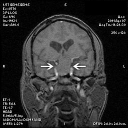

Unfortunately, the MRI did show a suprasellar mass which is affecting the optic chiasm and is responsible for the vision loss.

MRI did show a suprasellar mass which is affecting the optic chiasm and is responsible for the vision loss. The tumor was resected and was a benign pituitary tumor.      (0 votes)